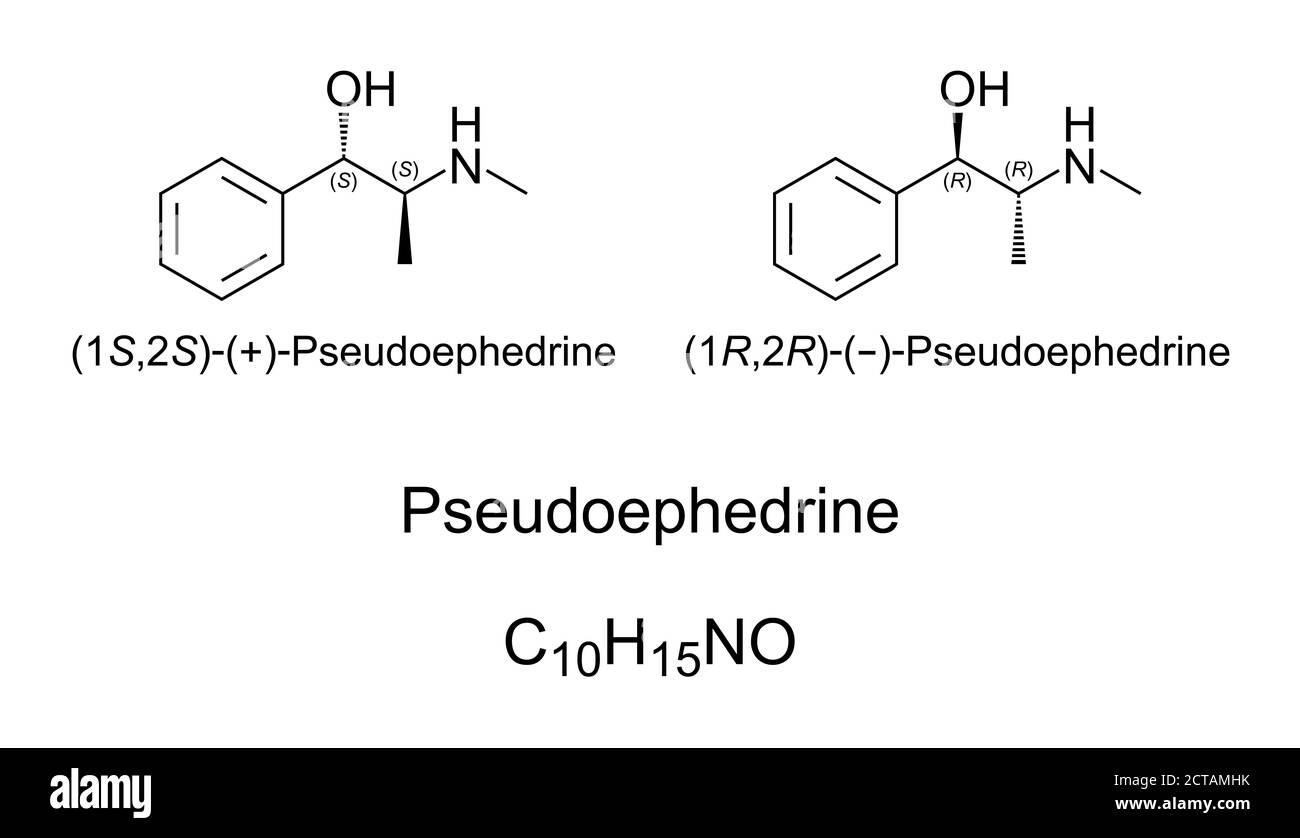

RF2CTAMHK–Pseudoefedrina, struttura chimica. Un decongestionante e stimolante. Utilizzato illecitamente da atleti e camionisti come agente drogante.